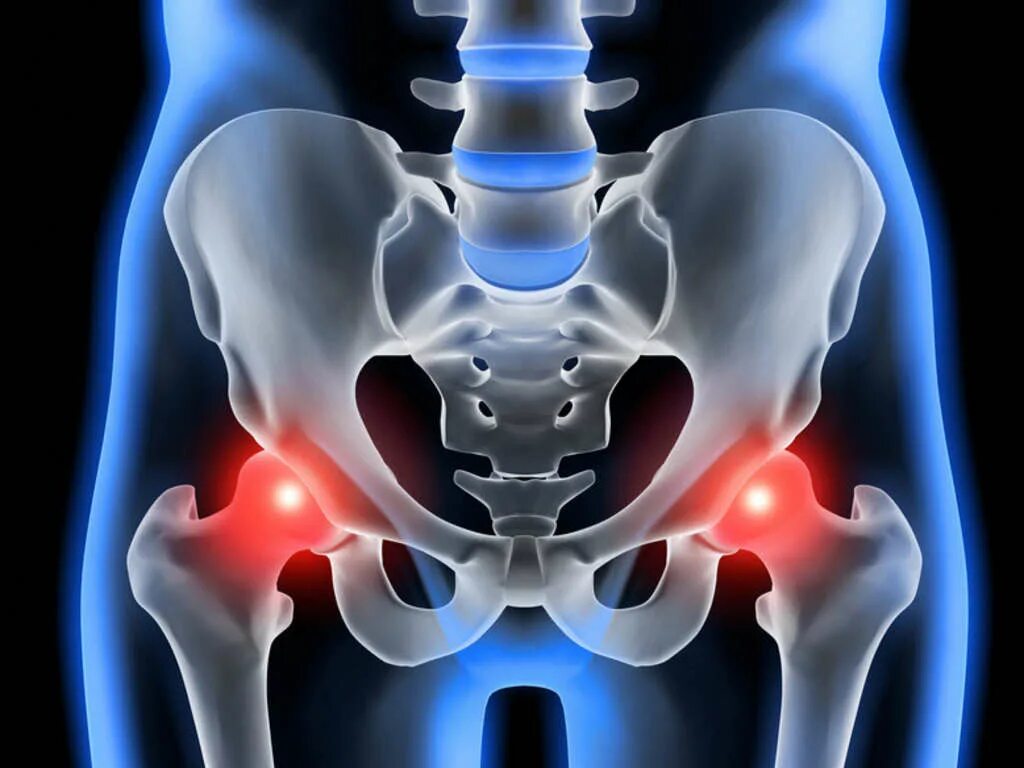

Тазобедренный сустав это